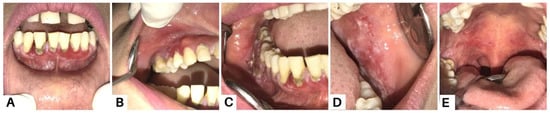

Figure 6.

Case 3, a 35-year-old woman, reported experiencing canker sores for the past three months. Initially, she sought treatment from a general dentist, receiving antibiotics, analgesics, and anti-inflammatory mouthwash. However, these treatments did not lead to recovery. Intra-oral examination revealed multiple erosive lesions with sloughing, and desquamative lesions on the upper and lower gingiva (A–C), buccal mucosa (D), and palate (E). Oral lesions are the first symptom in 50–70% of PV cases and affect 90% of patients, often preceding widespread mucocutaneous involvement by several months [8]. The most commonly affected areas include the buccal and palatine mucosa, lips, and gingiva. In PV, the erosions are characterized by their multiplicity, varying sizes, irregular shapes, peripheral extension, and frequent delay in re-epithelialization. Gingival involvement primarily presents as desquamative gingivitis [4].